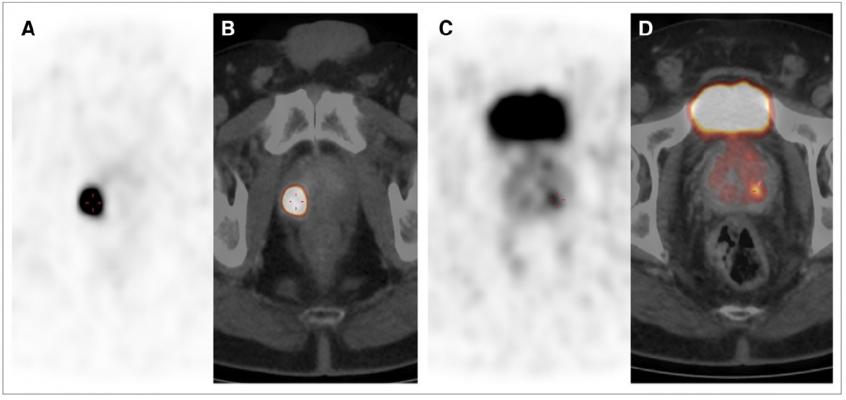

68Ga-PSMA PET/CT images showing multifocal PCA in peripheral zone with GS of 5 1 5 5 10. (A and C) Axial PET images. (B and D) Fused PET/CT images. SUVmax of lesion in B was 84.3 and that of lesion in D was 5.7. IRS was 3, and 80% of cells were stained. Credit: Senior author V Prasad, Charité Universitätsmedizin Berlin, Berlin, Germany.

The new study demonstrates that the maximum standardized uptake value (SUVmax) on Gallium-68 prostate specific membrane antigen (68Ga-PSMA) PET/CT scans correlates with PSMA-expression in primary prostate cancer. By this means, researchers were able to generate an SUVmax cutoff for the differentiation of cancerous and benign prostate tissue.

For the study, the data of 31 men (mean age of 67.2 years) who had undergone prostatectomies and preoperative PET scans were analyzed, with the SUVmax generated for suspicious areas and visually normal tissue. Both cancerous and benign prostate tissue samples (62 total) were stained with monoclonal anti-PSMA antibody. All the cancerous lesions could be confirmed histopathologically. The best cut-off value was determined to be 3.15 (sensitivity 97 percent, specificity 90 percent).

Prasad noted, “This validated cutoff of 3.15 for SUVmax enables the diagnosis of prostate cancer with a high sensitivity and specificity in both unifocal and multifocal disease.”